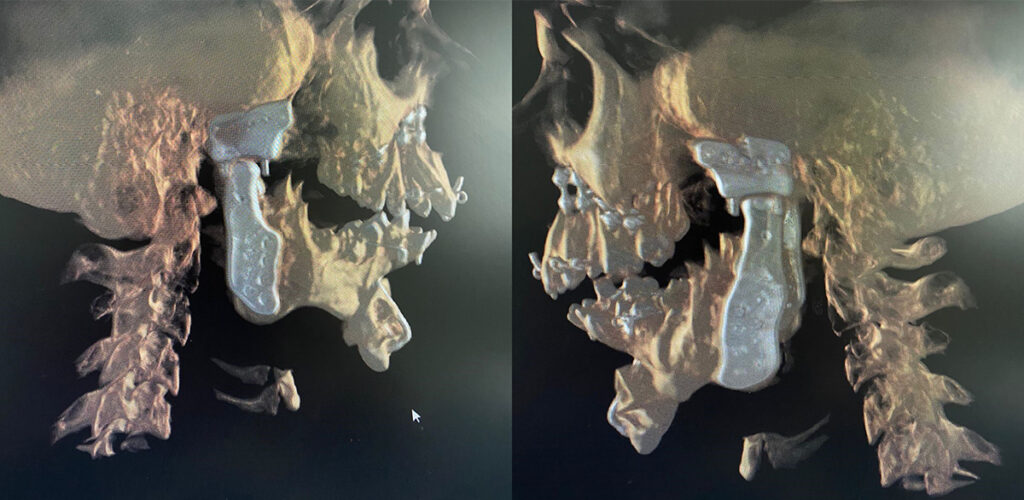

In the CT scan image shown here, you can see a large boulder-like enlargement of the joint. This is the ankylotic mass.

The post-operative CT scan showing the temporomandibular joints on both sides and the titanium miniplates used for fixation of the upper and lower jaw after bijaw orthognathic surgery.